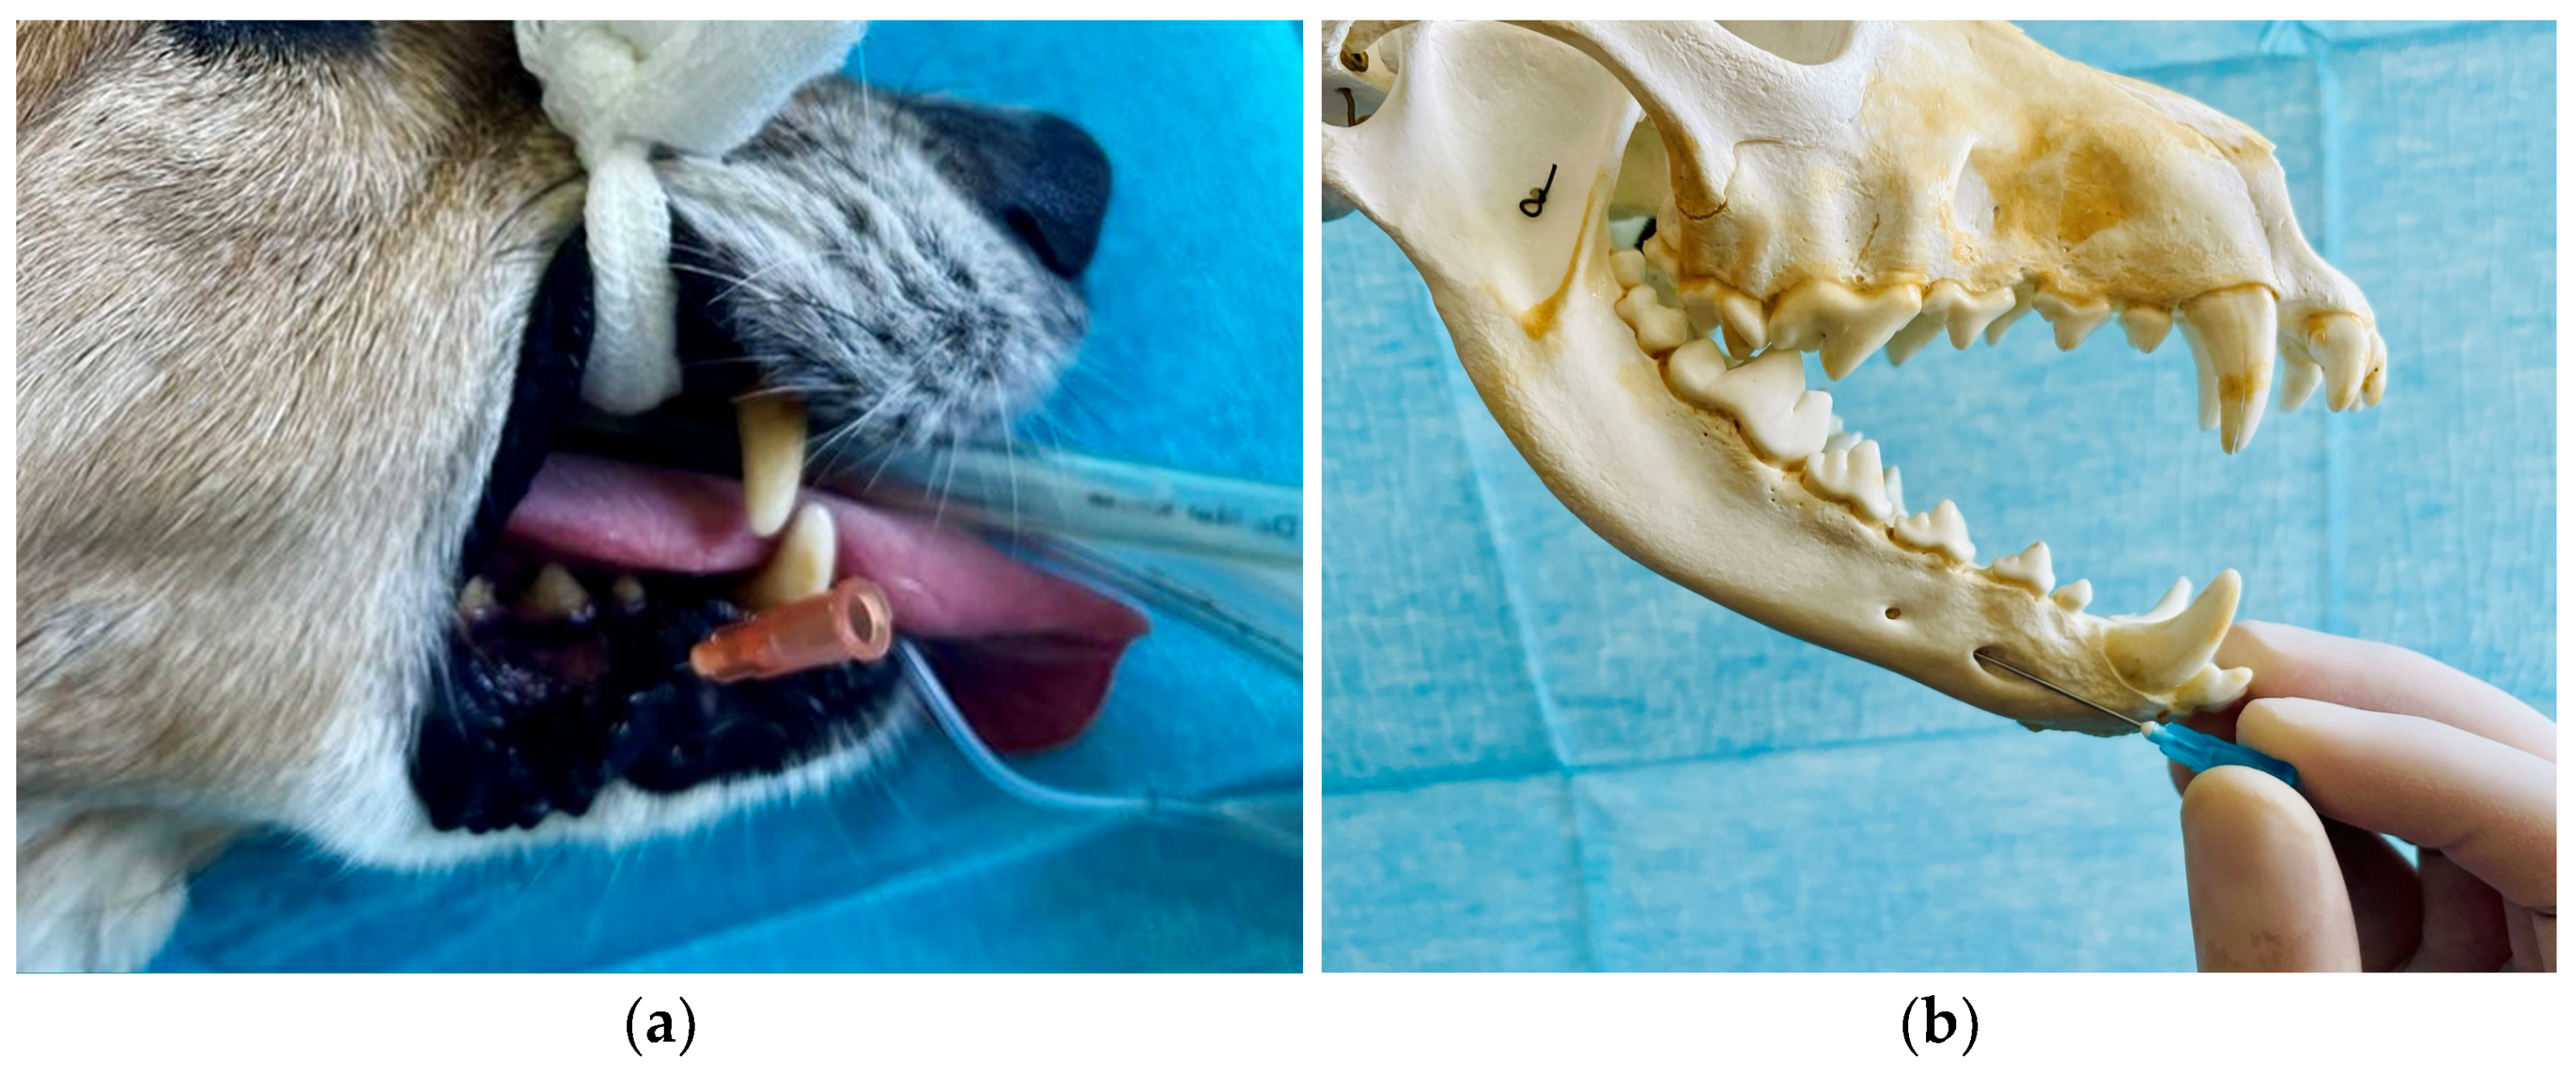

5. Local Anaesthesia of the Oral Region

5.4. Inferior Alveolar (Mandibular) Nerve Block

5.5. Mental Nerve Block